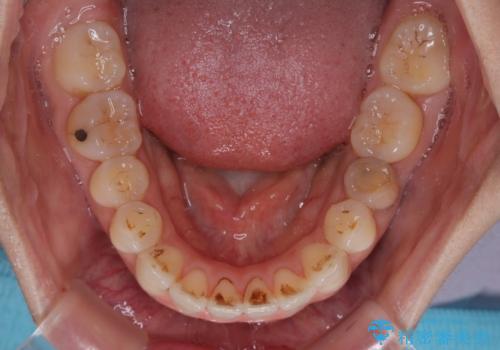

【モニター】飛び出した上顎前歯 補助装置を併用したインビザライン矯正治療

補助装置なしでも改善できる可能性はありましたが、補助装置で確実性を上げ、短期間できっちりと仕上げることができました。